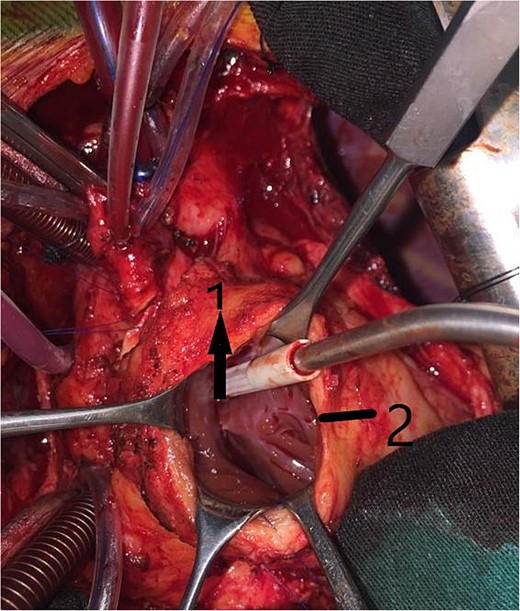

An 11-year-old girl was referred to our hospital with a main complaint of progressive exertional dyspnea. She had undergone surgical repair of SAS 6 years ago. Transthoracic echocardiogram (TTE) revealed the following findings: severe left ventricular hypertrophy, tunnel-like fibromembranous subaortic stenosis with a length of 10 mm, a peak gradient (PG) across the LVOT of 170 mmHg, and mild aortic regurgitation. Based on these findings, the patient was scheduled for elective surgical repair with a possible indication for MKO. The operation was performed via median sternotomy with great caution to avoid inadvertent rupture of any cardiac cavity due to heavy adhesions from the previous operation. The aorta was cannulated just below the takeoff of the innominate artery. Bicaval cannulation was performed to provide a bloodless field. Aortic cross-clamping was applied, and antegrade cold blood cardioplegic solution was administered via a catheter placed in the ascending aorta. The ascending aorta was opened transversely 1 cm above the sinotubular junction (Fig. 1). The aortic valve leaflets were examined carefully to confirm that the aortic valve could be preserved. LVOT was examined thoroughly, and it was clear that the stenosis in the subaortic area was so complex that simple resection through the aortic valve orifice would not be sufficient. The right ventricular outflow tract was opened transversely below the pulmonary valve. The conal papillary muscle was identified (Fig. 2). A right-angle instrument was introduced through the aortic orifice into the interventricular septum, and the tip of the instrument was used to perforate the conal septum to the left of the conal papillary muscle to prevent damage to the conduction system; the septal incision was completed with great caution to avoid damage to the aortic cusps and to extend the incision downward as necessary to completely relieve the stenotic subaortic area (Fig. 3). Interrupted 5/0 Prolene sutures were placed circumferentially around the septal incision to close the interventricular septal defect using a bovine pericardial patch to provide adequate widening of LVOT (Fig. 4). The right ventriculotomy was closed with a second bovine pericardial patch to avoid any possible obstruction of the right ventricular outflow tract (Fig. 5). The remainder of the operation was completed uneventfully. After 6 hours of mechanical ventilation, the patient was extubated, and she convalesced well postoperatively. TTE showed excellent results of the operation with PG across LVOT of 20 mmHg. On 1 year follow-up, the patient was asymptomatic and in very good general condition, and TTE findings confirmed the excellent result.

Intraoperative image showing the right ventriculotomy (2) and the conal papillary muscle (1).